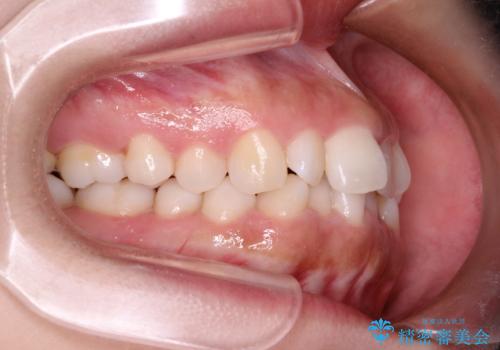

- 初診時には前歯部に捻転や叢生、臼歯部にも一部叢生が見られる状態でした。

インビザラインでの治療を計画し、行っていきました。

インビザライン治療により、捻転を含む歯列もしっかりと改善しています。

基本的な不正咬合部分は初回の30枚のマウスピースでほぼ改善しており、リファインメントでは前歯部の細かな調整など、患者様の要望を取り入れる形でシミュレーションをセットアップし、満足の行く結果に仕上がりました。